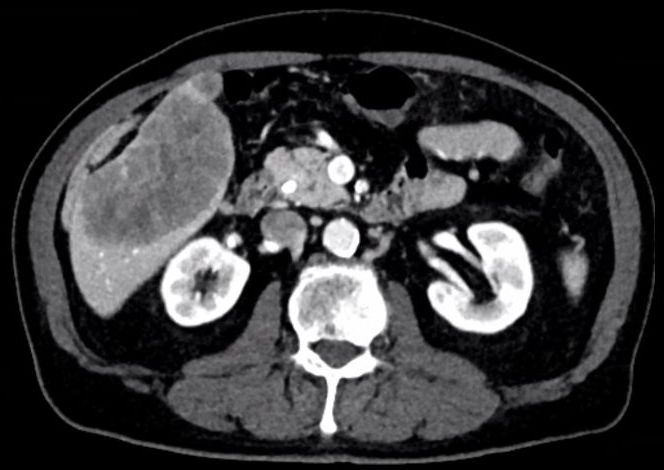

75-jähriger Mann mit Herdbefund in der Leber. Nach Kontrastmittel ist der Herd in der arteriellen Phase hypodens. ![]() | |